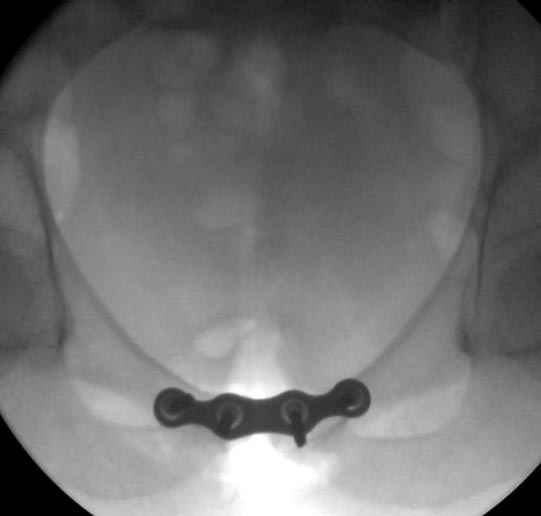

Здесь слайды случая больного с политравмой, включающей сегментарный перелом бедра и повреждение таза с нарушением тазового кольца, разрыв симфиза и перелома крестца зон 2 и 3.

На множественных слайдах важные моменты операции. Хотел бы подчеркнуть, как важно иметь возможности всех необходимых ренгенограмм, включая компютерную томографию и стандартных внутритазовых рентгенограмм (инлет и оутлет).